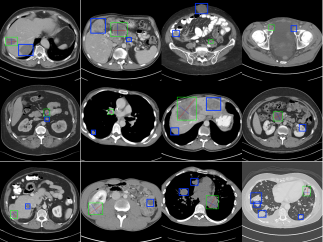

For the lesion mining results, our method surpasses all other methods by a large margin. specifically, it outperforms the current state-of-the-art method [12] by 2.3% of the average sensitivity and 2.7% average precision, proving that our end-to-end method has better lesion mining capacity. We show some lesion mining results in Fig. 3. The green bounding boxes represent the original annotations. The mined lesions are shown in blue. In total, we mined about 8000 suspicious lesions on the DeepLesion training set.